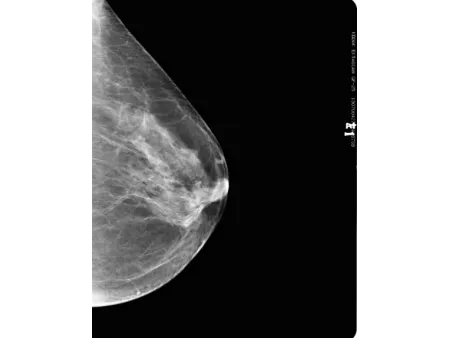

El detector plano CMOS, reconocido por su alta sensibilidad, permite obtener imágenes mamarias con gran nivel de definición. Este mamógrafo también incluye el software especializado Console, que utiliza algoritmos avanzados de posprocesamiento para mamografía, facilitando la visualización de estructuras finas y mejorando la precisión en la interpretación clínica. Con una capacidad de resolución de 60 líneas por centímetro, es capaz de detectar microcalcificaciones tan pequeñas como 0.1 mm, lo que refuerza su utilidad en programas de detección precoz de cáncer de mama y en evaluaciones clínicas más específicas.